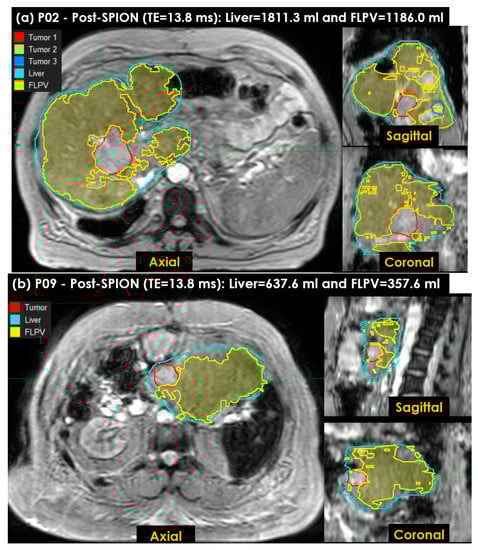

Figure 7 shows the FLPV identified in the auto-contouring tool with the THRES-MEANR2* of the PRE-POSTR2* approach. The FLPV was clearly identified with minimal overlapping for three tumors in patient P02 (Figure 7a) and a tumor in P09 (Figure 7b). The FLPVs in patients P02 and P09 were 1186.0 mL (65.5%) out of 1811.3 mL and 357.6 mL (56.1%) out of 637.6 mL, respectively. P02 had three tumors, contoured in red, (Tumor 1), green, (Tumor 2) and blue, (Tumor 3). P09 had a single tumor, contoured in red. All tumor illustrations demonstrate the efficiency of auto-contouring the FLPV on axial, sagittal and coronal 3D planes.

Figure 7. The functional liver parenchyma volume(s) FLPV(s), identified using the THRES-MEANR2* of the first PRE-POSTR2* approach in an auto-contouring in-house tool, were overlaid on liver images. (a) Three tumors in patient P02, contoured in red (first tumor), green (second tumor) and blue (third tumor), are illustrated to demonstrate the efficiency of the in-house tool for identifying the FLPV; (b) a single tumor in patient P09, contoured in red, is also illustrated. Both FLPVs of P02 and P09 are clearly distinguished from all tumors with minimal overlapping between the FLPV and non-FLPV (tumor, hepatic vessels, liver fibrosis and scarring associated with hepatic cirrhosis).